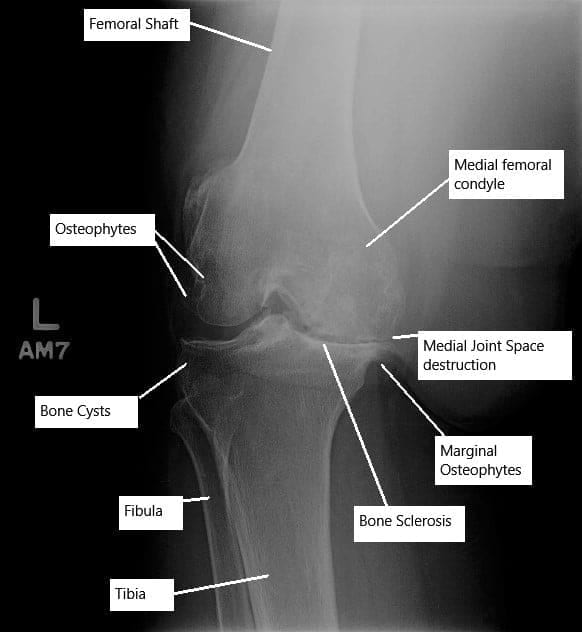

La destrucción del cartílago continúa, lo que provoca una disminución del espacio articular visible en las radiografías de articulaciones grandes. El cartílago degenerado se disuelve en la articulación o forma »cuerpos sueltos» dentro de la articulación. T

Su cuerpo intenta reparar el hueso expuesto resultante del cartílago desnudado. La reparación conduce a un engrosamiento y crecimiento excesivo del hueso subcondral. El engrosamiento del hueso subcondral es especialmente prominente en los lados de la articulación, que aparecen como espolones óseos.

La membrana sinovial de la articulación sufre hiperplasia, que se hincha e inflama. Se desarrollan quistes/cavidades en el hueso subcondral en los lugares de mayor estrés. La presión dentro de la articulación aumenta como resultado de una disminución del flujo venoso y un aumento del flujo arterial en la región subcondral. El aumento de la presión provoca síntomas de dolor en reposo.

Las radiografías simples suelen ser la primera prueba radiológica realizada para buscar reducción de espacio articular, quistes y engrosamiento de huesos. En algunos casos, para una evaluación detallada, puede solicitarse una tomografía computarizada o una resonancia magnética. Una resonancia magnética proporciona los detalles de todas las estructuras de tejidos blandos dentro de la articulación, que no son visibles en una radiografía.